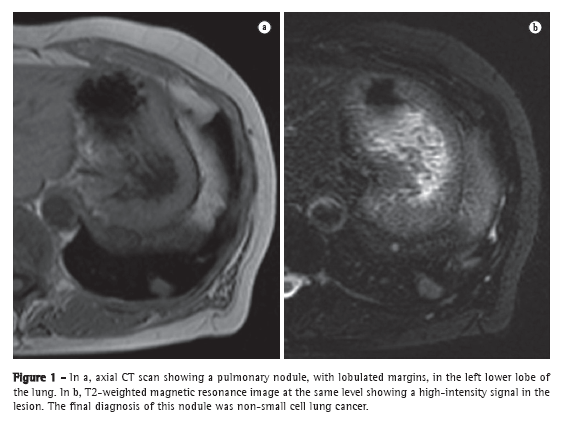

Treatment initiation and follow-up

After it has been decided whether patients should receive specific treatment, it is important to establish the clinical severity of the initial presentation of the disease. The fact that certain prognostic markers are major indicators of disease severity in patients with PH has been established in the literature. The following have been associated with a worse prognosis: functional classes III and IV; an increase in brain natriuretic peptide (BNP) or N-terminal-pro-BNP levels; 6MWD < 330 m; maximal oxygen uptake during the cardiopulmonary test < 12 mL/min/kg; and hemodynamic variables (RAP > 8 mmHg and cardiac index ≤ 2.0 L/min/m2 ).(27,51-53) Patients with markers of severity should be considered candidates for intravenous therapy in countries where this treatment is available. In localities where intravenous therapy is unavailable, combination therapy can be given at the initiation of treatment. However, it should be highlighted that there have been no clinical studies validating this approach; nevertheless, this approach has been considered in the latest international algorithms (Chart 3).

After the initiation of treatment, patients should be reevaluated, generally every 3-4 months, through analysis of the symptoms, physical examination findings, 6MWD, and BNP levels, in order to assess the response to treatment and decide the course of action. In localities where the 6MWT cannot be performed in a corridor, functional evaluation can be performed by means of a treadmill 6MWT, a protocol that has previously been validated for use in patients with PH.(54) If patients present clinical improvement or stabilization, as well as improvement or stabilization of the aforementioned markers, the treatment should be maintained; otherwise, an investigation should be performed in order to find the cause of treatment failure and avoid clinical deterioration. Infection, dietary noncompliance (excessive ingestion of salt or fluids), or the inappropriate use of the drugs are common causes of decompensation. If an evident cause is not found, a new hemodynamic evaluation can be performed, and, if hemodynamic worsening is confirmed, the specific treatment should be optimized by increasing the dose or adding another class of drugs. Patients who present with progressive worsening despite the optimized clinical treatment should be referred for an evaluation for lung transplantation (Figure 5).(55)